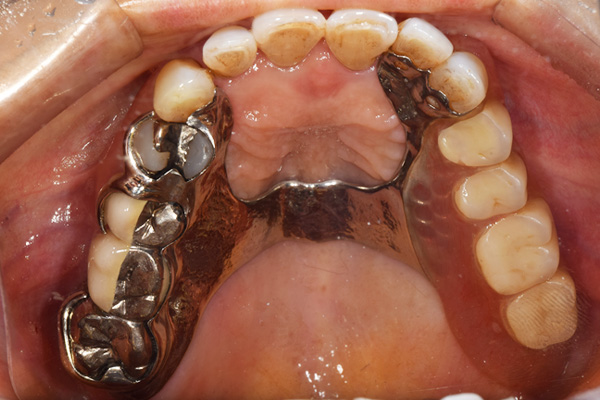

ケース2(自費の総入れ歯と部分入れ歯)

上下の入れ歯が外れやすくなったということでいらっしゃいました。 顎の骨はしっかりしていましたので、精密な型取りさえすればしっかりした入れ歯がつくれると思いました。 また下には6本歯が残っていましたが、虫歯になっている歯もありました。 かぶせ物のなかで大きな虫歯があった歯があり、1本だけ残せない状態でした。

上の入れ歯は確かに吸着は甘くなっていました。 また下の入れ歯はバネの一部が壊れており、安定感がなくなっていました。

精密な型取りの後、噛み合わせのチェックをしていきました。 かぶせ物も同時に作っていきました。

歯を並べた後、かぶせ物のフレーム作ってもらいました。先に歯を並べて理想の位置を決めておくことが大切です。

完成した入れ歯とかぶせ物です。 入れ歯への寛容度が高い患者様でしたので、 金属は使用せず、プラスチックのみで上は仕上げました。 下顎も歯は1本減ってしまいましたが、しっかり 入れ歯が維持できる様な構造にしました。

お口の中に入れた状態です。 見た目も最初とほとんど変わることなく作成できました。 維持や吸着に関しても問題ないようでした。

年齢 80歳・女性

主訴 上下の入れ歯が外れやすくなった

治療期間 3ヶ月

治療費 .メタルボンドクラウン:550,000円

.義歯:990,000円(税込、上下)

治療方針 長年使ってきた義歯の人工歯が磨耗し、臼歯部での咬合がすくなくなり、入れ歯の安定も悪くなり、あたりどころが悪くなって痛みが出ている。 そのため、入れ歯を上下作りかえる必要がある。

治療内容 過去に治療を行ったことのある歯が再度虫歯になってしまっているところがあり、すでに残せない状態にまでなっていたため、歯を一本抜歯した。 その後、かぶせ物と入れ歯を同時に作成していった。

特記事項 歯を抜いた後は、2〜3ヶ月歯ぐきの回復を待ってから入れ歯を作るため、待機期間があります。その間、古い入れ歯を調整しながらそのまま使うか、新し物をつくっておく必要があります。ただし、入れ歯は保険治療で作成する場合、6ヶ月は新しいものが作れないという決まりがあるので保険で全て作りたい場合は注意が必要です。